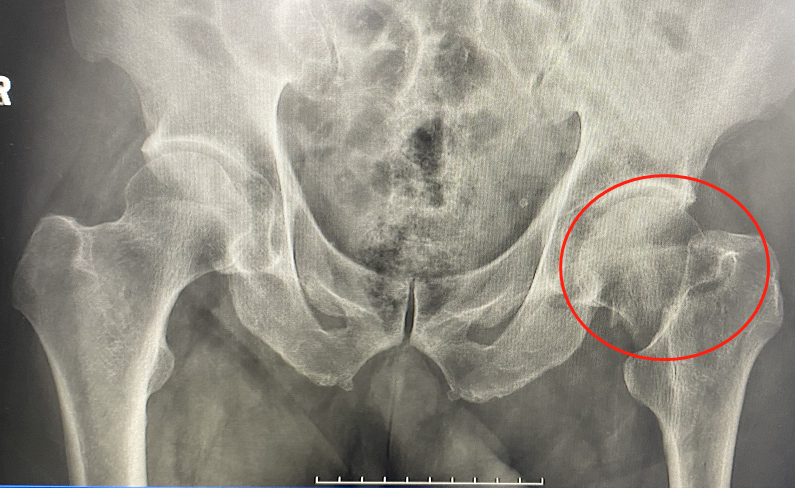

▲手術前左側股骨頸骨折

不久前,85歲的陳大爺?shù)沽?,左髖疼痛,不能坐立,只能平躺,左下肢不能活動。拍片結果顯示為 “左側股骨頸骨折”。這可愁壞了陳大爺?shù)膸讉€兒女,骨科徐光輝副主任醫(yī)師在對老人家的心肺功能,一般情況做過評估后,建議骨科微創(chuàng)手術,避免產生因骨折臥床的長期并發(fā)癥,又能讓老人家早日恢復,最大程度保證老人骨折前的生活質量。